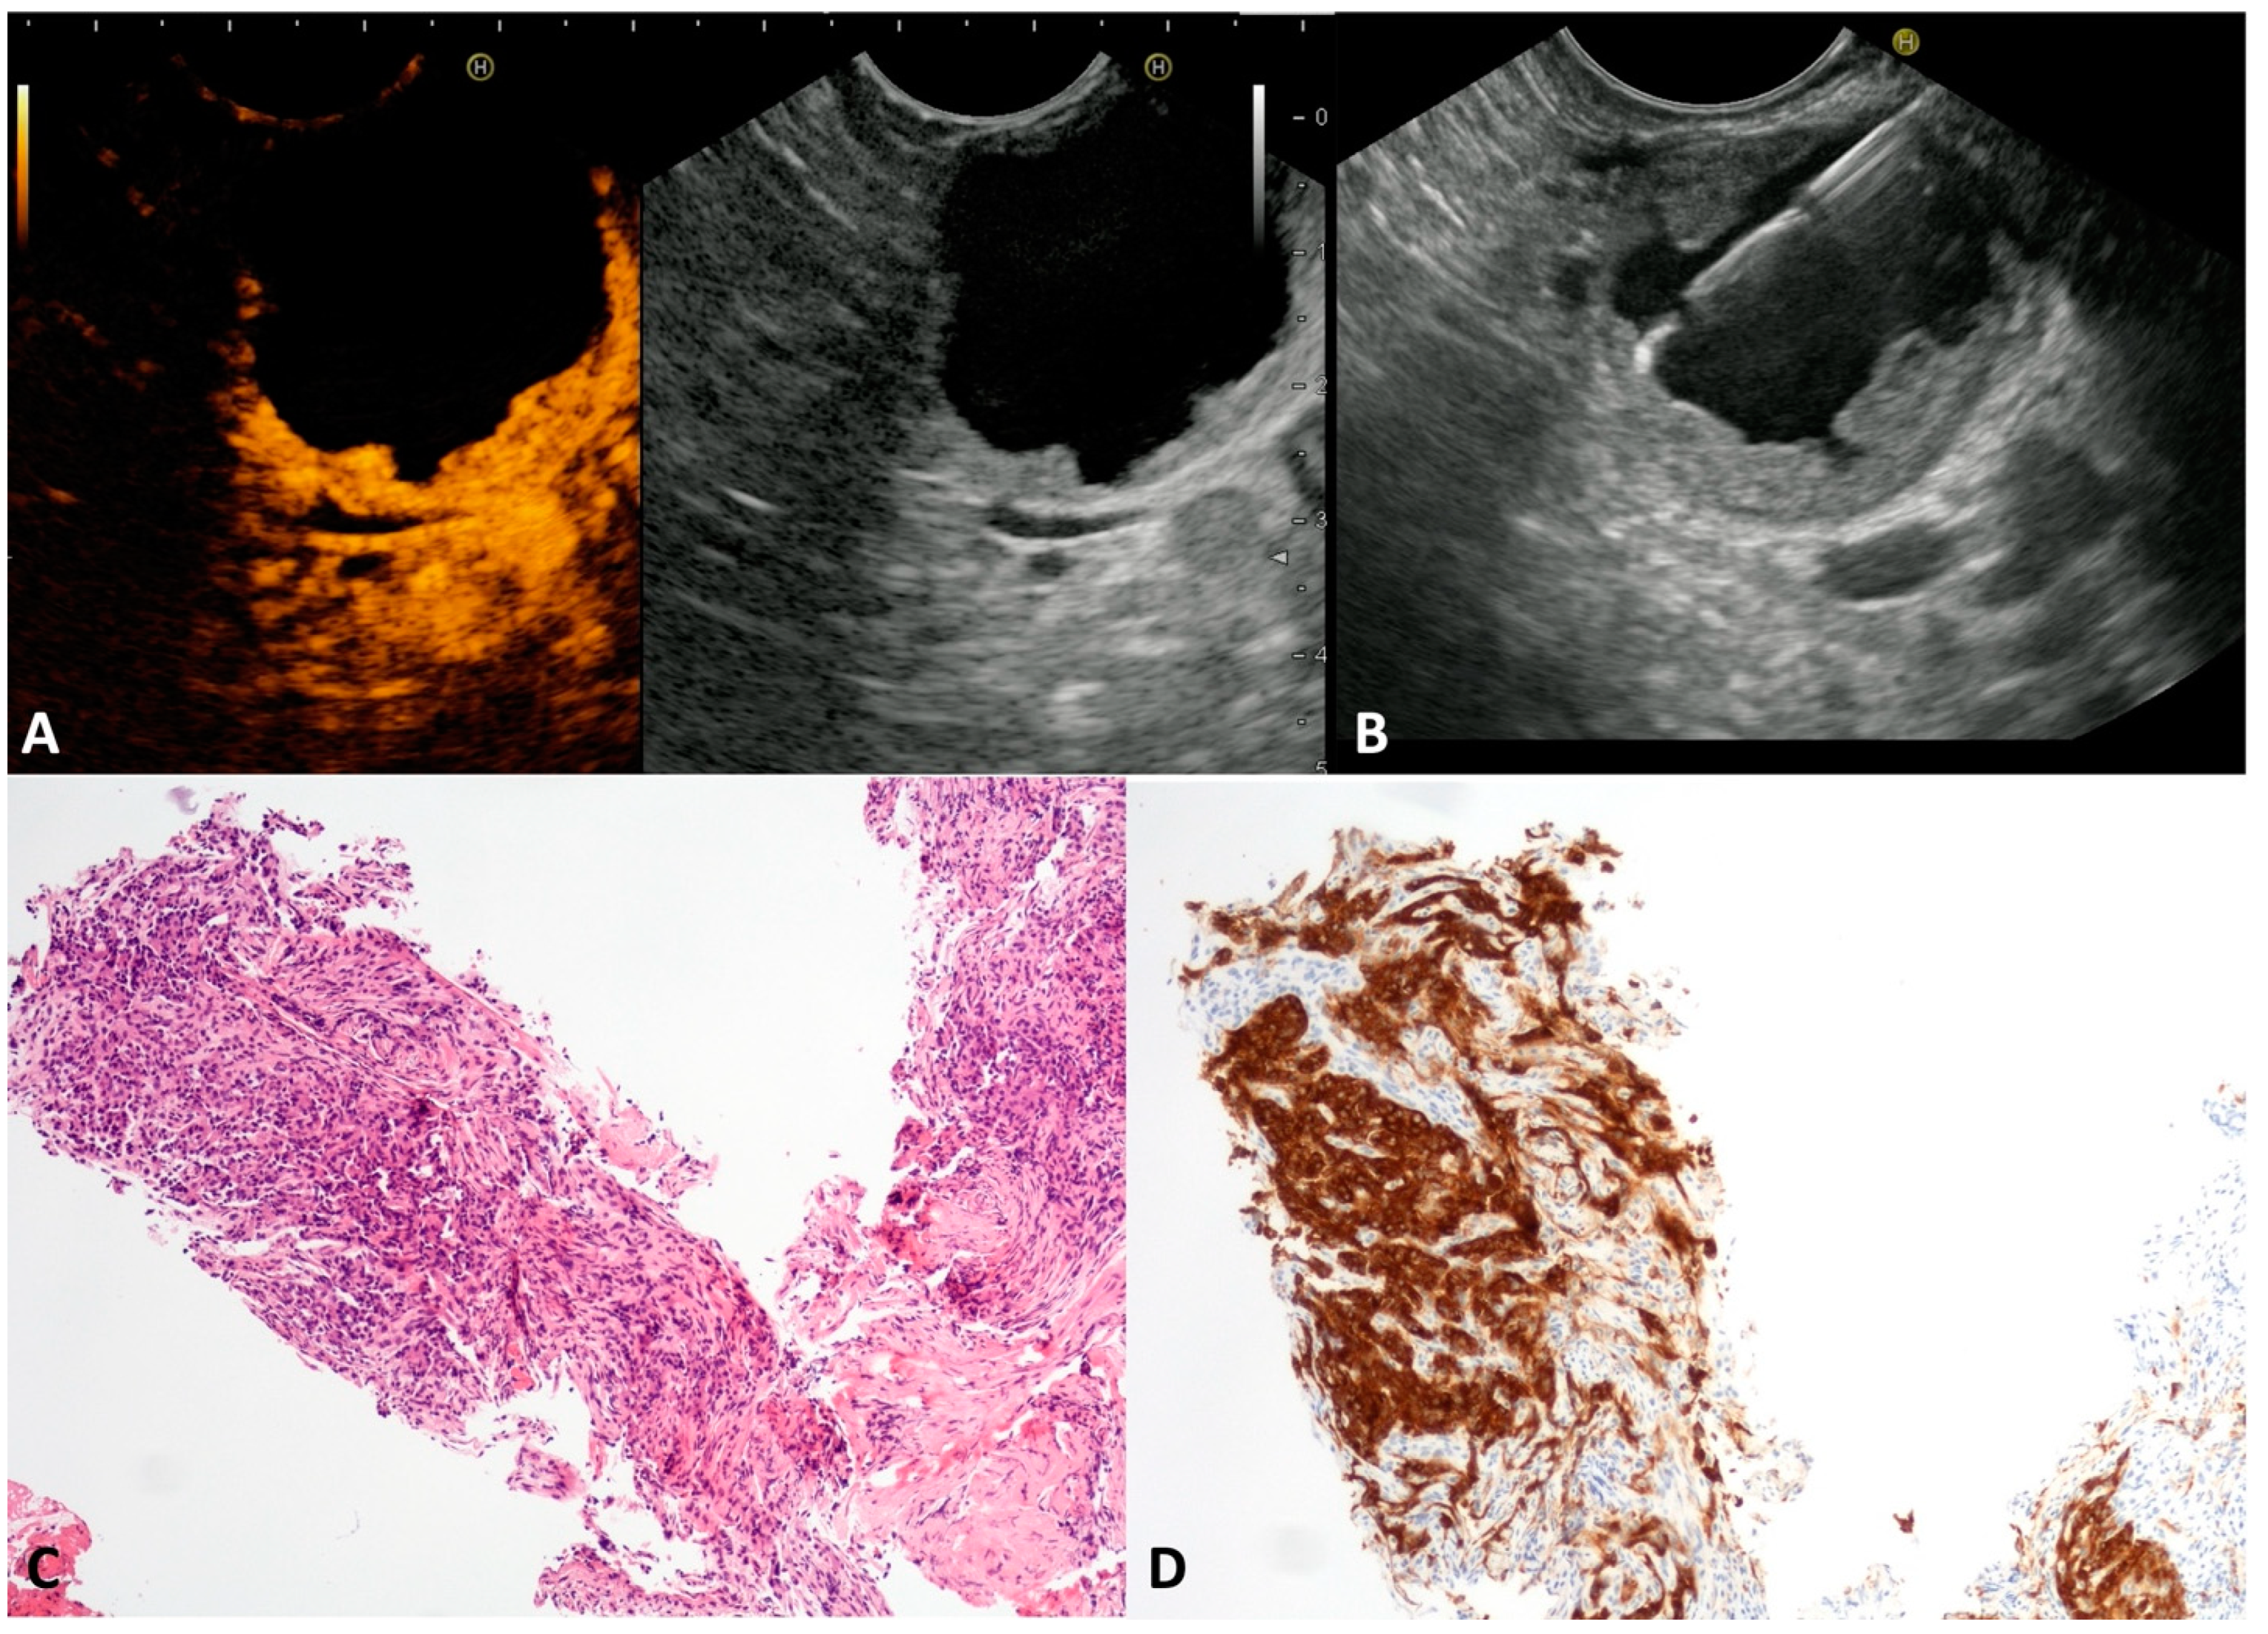

The published literature has reported that cNETs account for 13% of all pancreatic NETs []. Despite small cystic spaces in the context of a solid tumor being common in pancreatic NET, often assuming a “bull-eye” appearance with a central cyst and thickened wall, the complete cystic appearance is rare, and tendentially more indolent. cNETs may be sporadic or associated with multiple neuroendocrine neoplasia (MEN), or the von Hippel–Lindau or Wermer syndromes []. In our series, seven asymptomatic patients (four males, mean age 53 ± 6.8 years) presented a unilocular cyst (mean size 25.8 ± 6.7 mm) with a thickened wall (Figure 2A) located in the head, in the body, and in the tail of the pancreas in one, two and four cases, respectively. At CH-EUS, the hyperenhancement of thickened walls was observed (Figure 2B). The TTNB gathered histological specimens suitable for immunohistochemical stains in all cases. Numerous small round cells (Figure 2C) positive to chromogranin A and synaptophysin stains (Figure 2D) confirmed the neuroendocrine nature of the cysts. The evaluation of the proliferative index (Ki-67) of the TTNB specimens was possible in 6/7 (85.7%). All tumors were G1. Four out of seven patients underwent surgical resection that confirmed the preoperative diagnosis and the tumor grading. The remaining patients continued to be observed, with no changes over the follow-up period.

Figure 2.

Cystic neuroendocrine neoplasm. Contrast-harmonic endoscopic ultrasound showing hyper-enhanced walls of an unilocular cyst (A). Endoscopic ultrasound-guided through-the-needle biopsy targeting the thickened walls (B). The cyst wall is almost completely composed of small, tightly packed epithelial cells (C) that stain intensely for the neuroendocrine marker Synaptophysin (D). Hematoxylin–eosin original magnification ×100 (C). Synaptophysin original magnification ×100 (D).